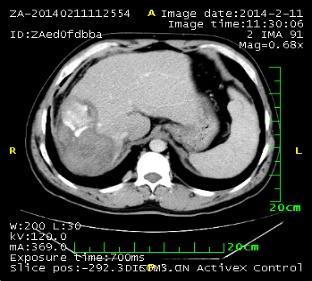

2. 肺部病灶治疗前后核磁对比:

肺部转移病灶在用药后2个月明显缩小,4个月后病灶基本消失。

治疗前

治疗2个月

治疗4个月

治疗6个月

治疗16个月